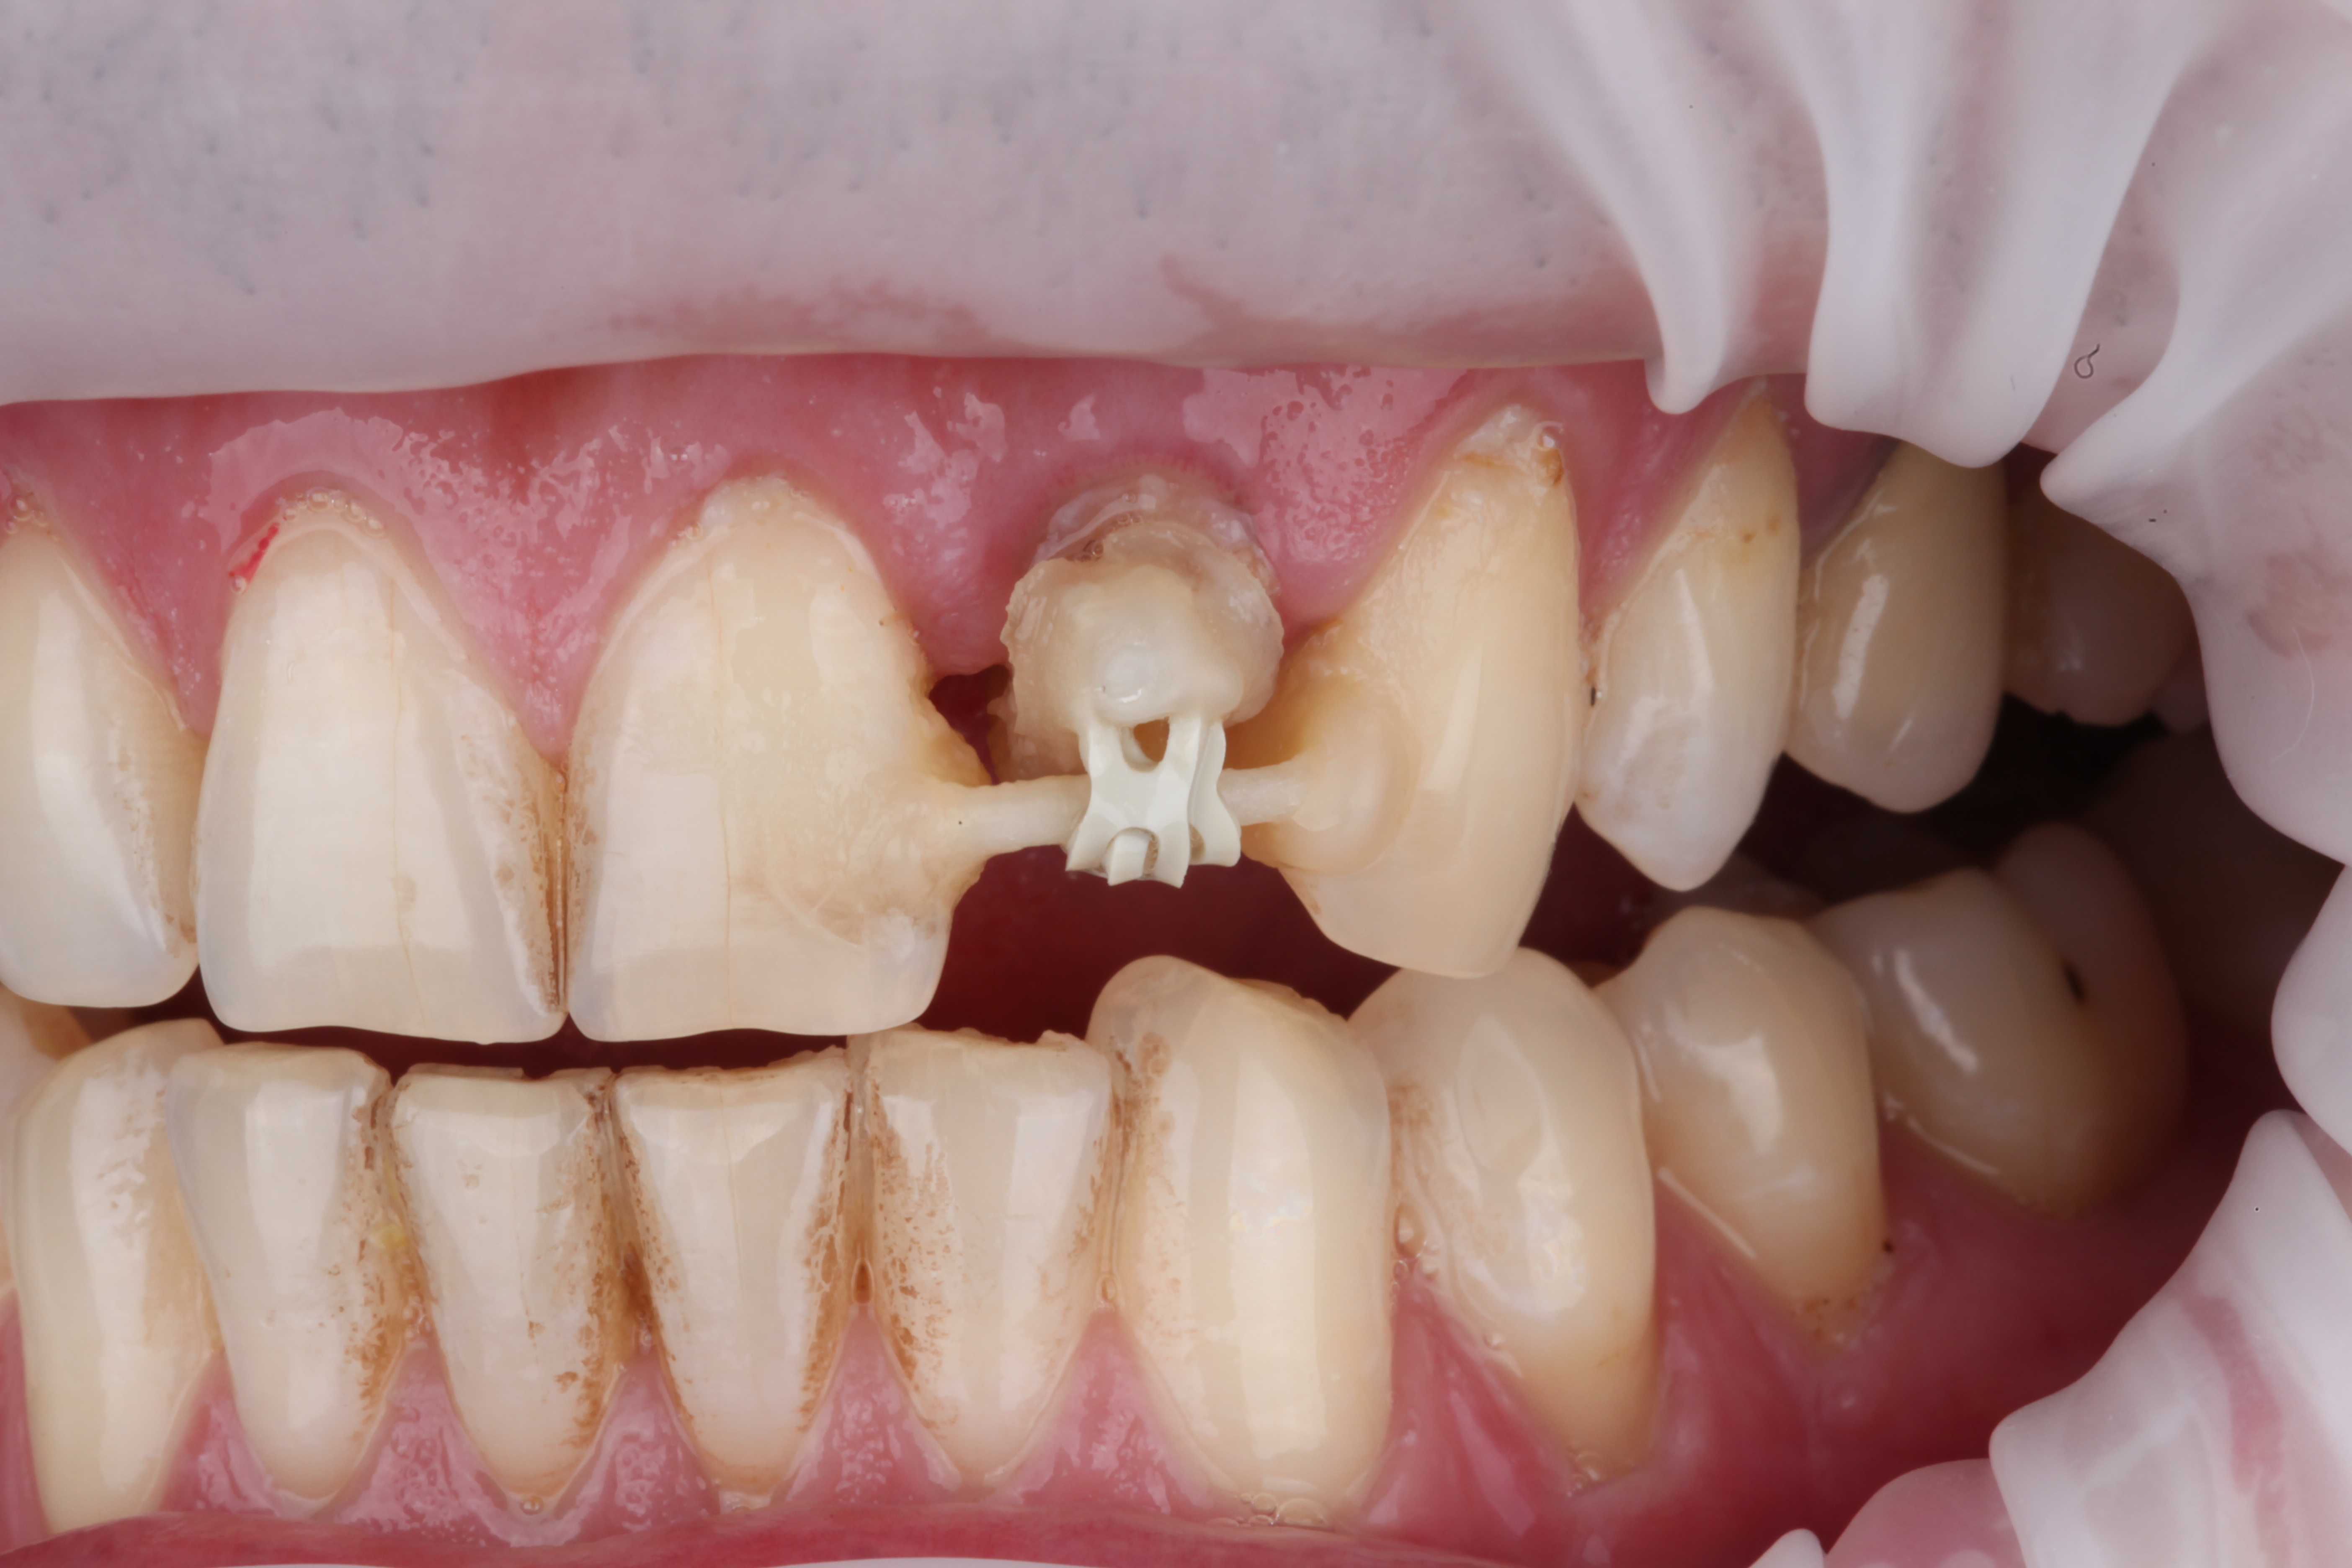

Зафиксирован стекловолоконный штифт и ортодонтическая тяга для вытяжения зуба.